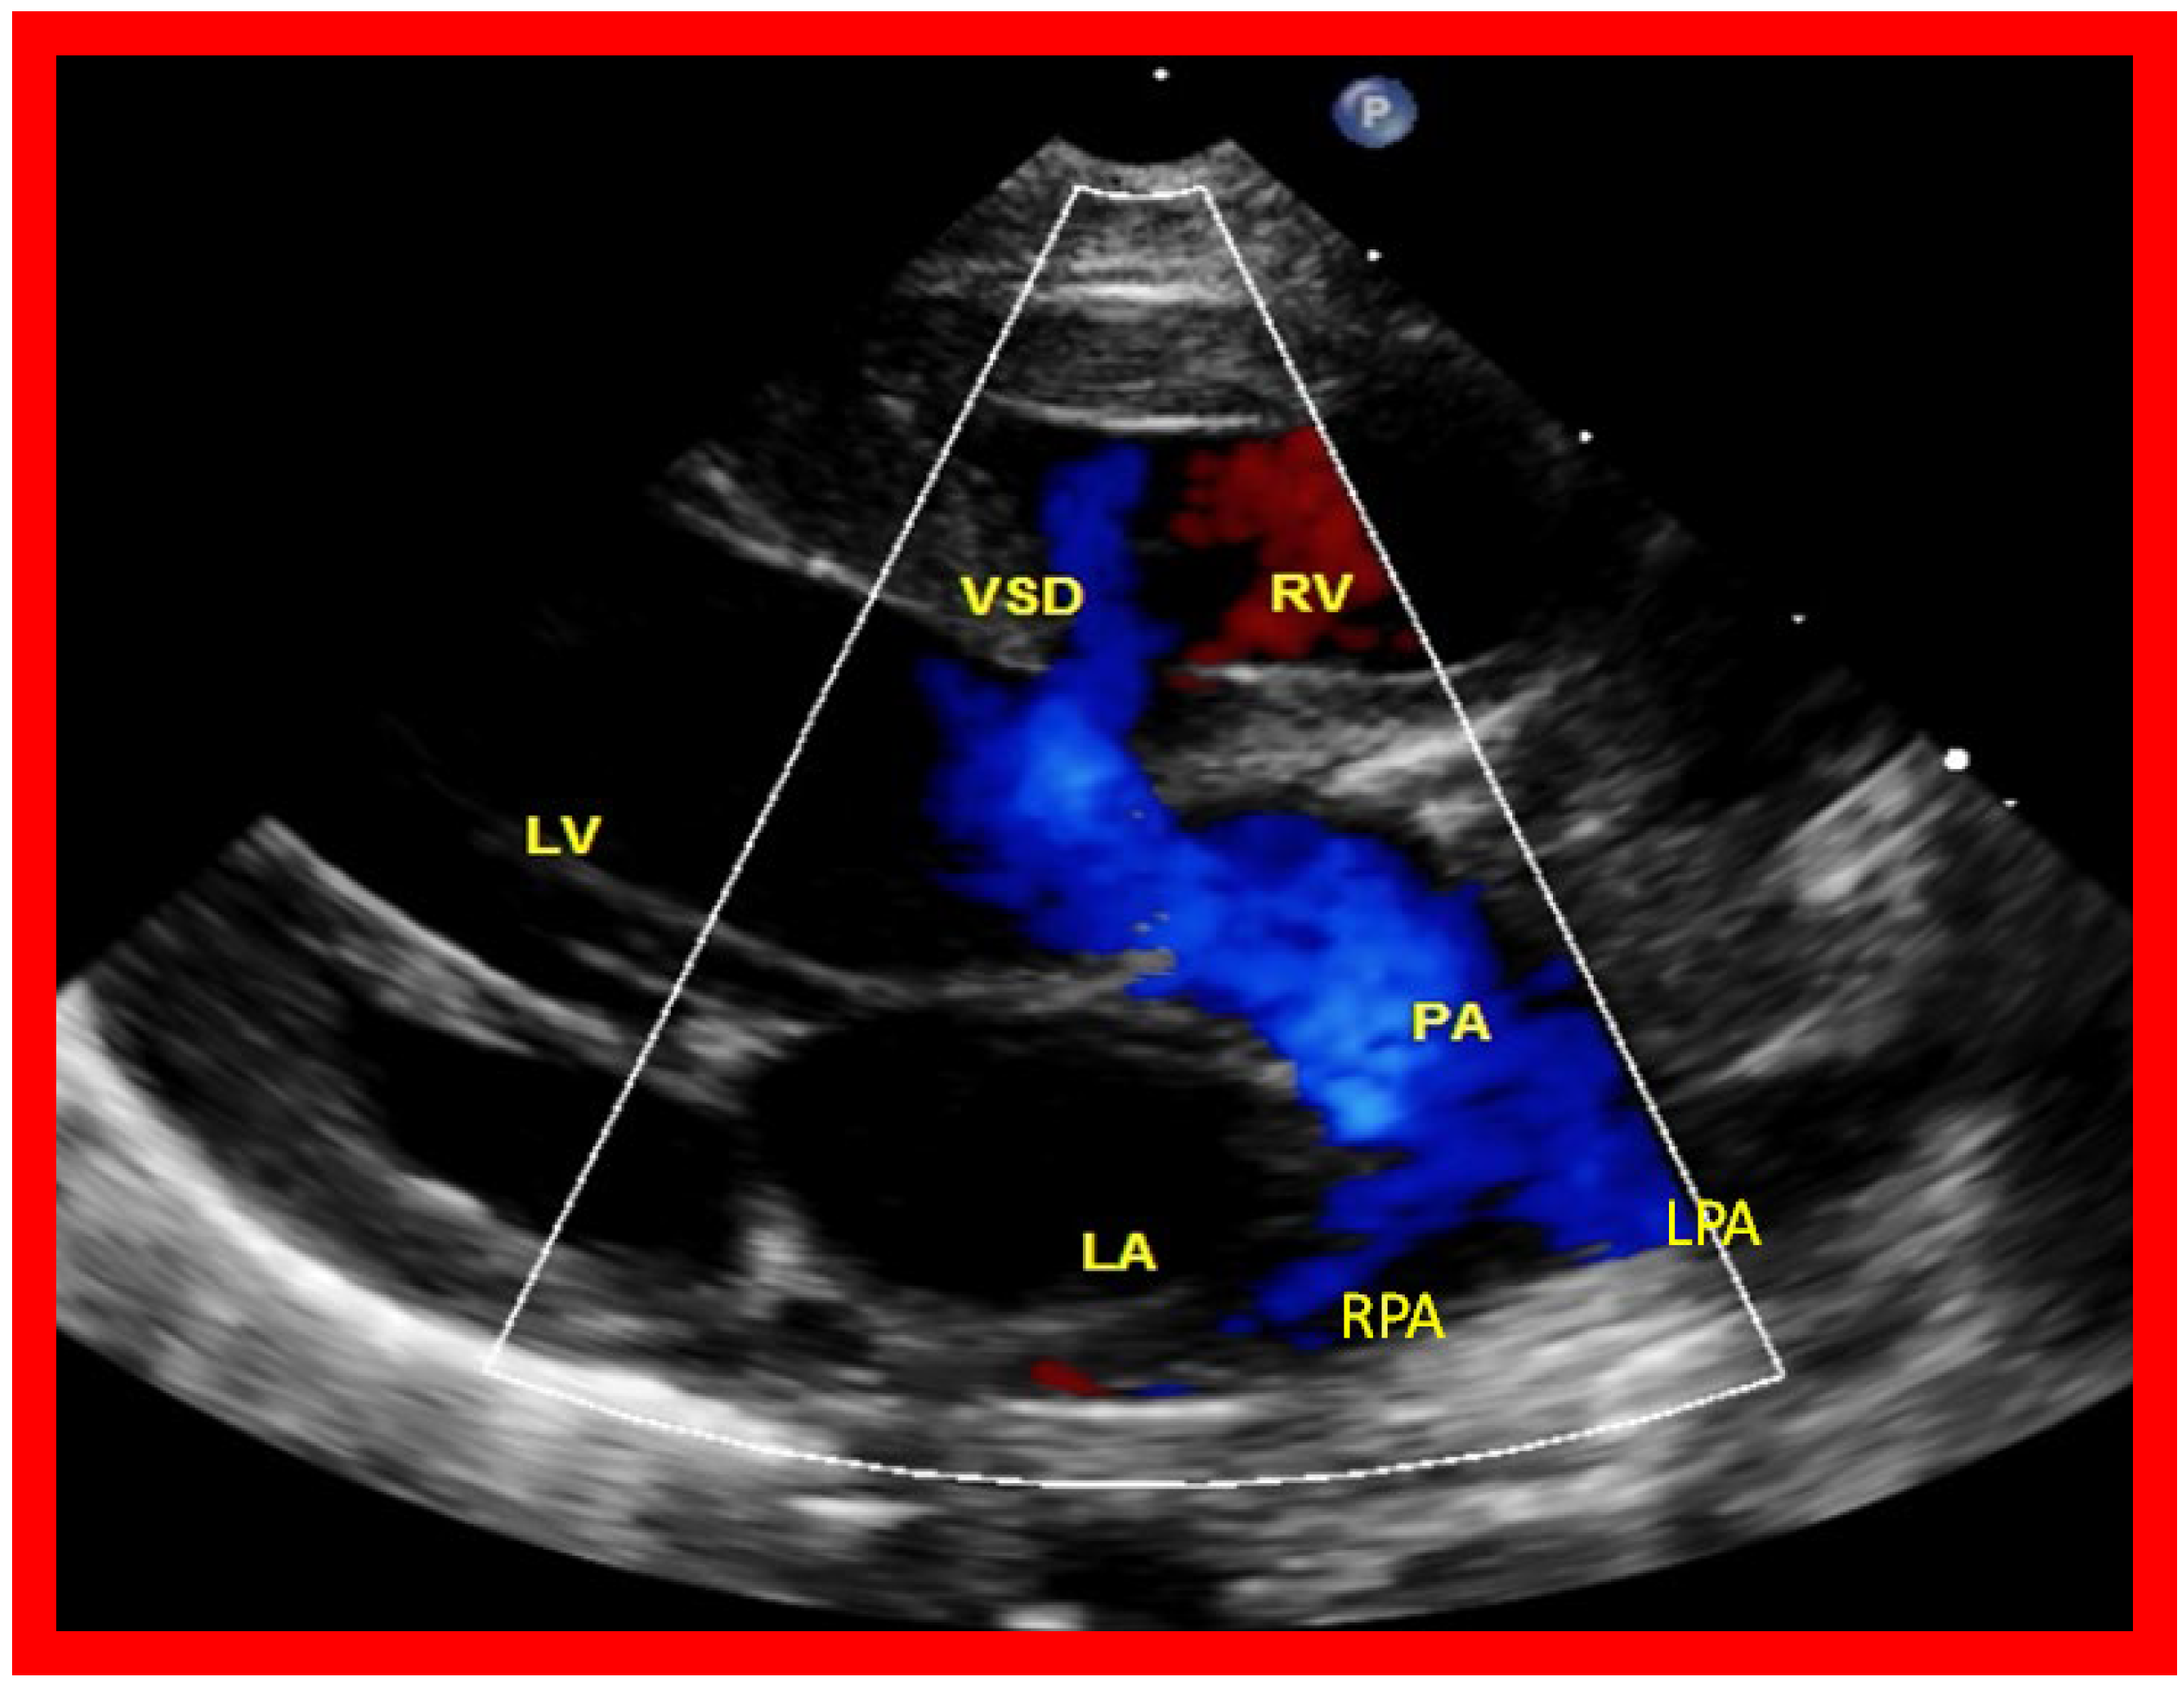

The relationship of the great arteries is examined next in order to classify them into various types, as mentioned above. The relationship of the great arteries (Figure 2, top) is established by following the vessels arising from the ventricles until the pulmonary artery (PA) bifurcation or aortic arch. In Type I patients with normally related great arteries, the aorta arises from the LV (Figure 5) and in Type II patients with transposition of the great arteries, the PA arises from the LV (Figure 6; Figure 7). In Type II patients, the blood vessel arising from the LV should be traced to demonstrate its branching into the right and left PAs (Figure 6; Figure 7). In Type III patients, it may be a little more difficult to assign the great artery relationship and, sometimes, other imaging studies, including angiography, may be needed to define the great artery relationship. In Type IV with truncus arteriosus, the limited data suggest that this can be performed by echocardiography (Figure 8; Figure 15). In the example shown [22], the atretic tricuspid valve (Figure 8a and Figure 9a), VSD (Figure 8b and Figure 9b), hypoplastic RV (Figure 9a), single vessel (truncus) arising from the heart (Figure 8c,d, and Figure 9c,d), and origin of the PA and its division into branch PAs (Figure 8d, and Figure 9c,d) were demonstrated.

Figure 7. A selected video frame from a parasternal long axis view with color flow mapping of another patient with tricuspid atresia and transposition of the great arteries demonstrating the left atrium (LA), left ventricle (LV), a small right ventricle (RV) and a moderate sized ventricular septal defect (VSD). The vessel coming off the LV bifurcates into right (RPA) and left (LPA) pulmonary arteries. Reproduced from Reference [21]. PA, pulmonary artery.